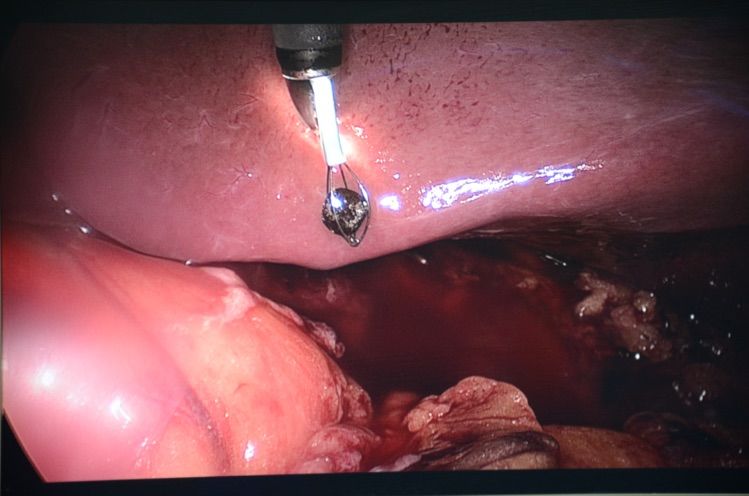

腹腔鏡下肝下異位闌尾切除,如爲(wei)傳(chuan)統闌尾麥氏切口,恐怕要延長(zhang)10CM左右切口。